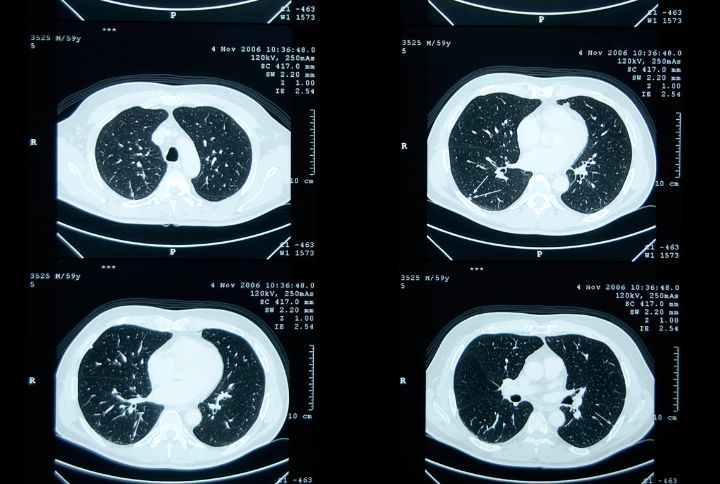

Nodule pulmonaire scanner

Les nodules pulmonaires sont le plus souvent détectés lors d’un scanner thoracique, plus rarement avec une radiographie. Cette découverte peut être fortuite ou résulter d’une surveillance médicale pour diverses raisons.

Petits et grands nodules au poumon

Les nodules de petite taille peuvent faire l’objet d’un contrôle par scanner à une date ultérieure, parfois après un traitement antibiotique;

Les nodules plus volumineux ou présentant des caractéristiques suspectes nécessitent des examens approfondis, tels qu’une fibroscopie bronchique, une écho-endoscopie, une ponction trans-thoracique ou, encore, un PET-scan. Ce dernier, combinant scanner et scintigraphie, permet d’évaluer l’activité du nodule.

Scanner thoracique normal ou anormal

Si les résultats sont rassurants, un suivi régulier par scanner est généralement recommandé, parfois sur plusieurs années. L’évaluation prend également en compte les facteurs de risque du patient.